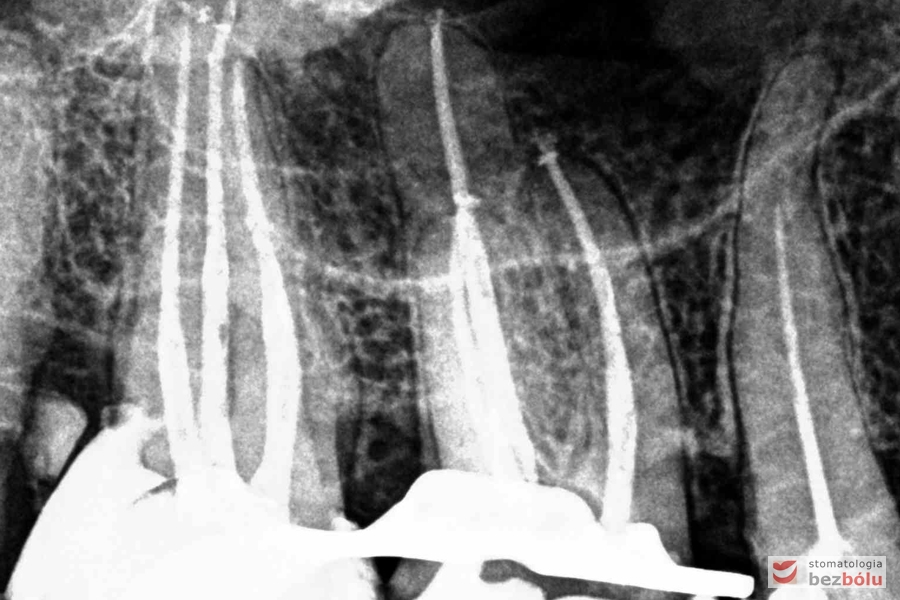

Radiowizjografia - szóstka, piątka, czwórka prawa w szczęce, wszystkie kanały niedopełnione

Radiowizjografia – szóstka, piątka, czwórka prawa w szczęce, wszystkie kanały niedopełnione